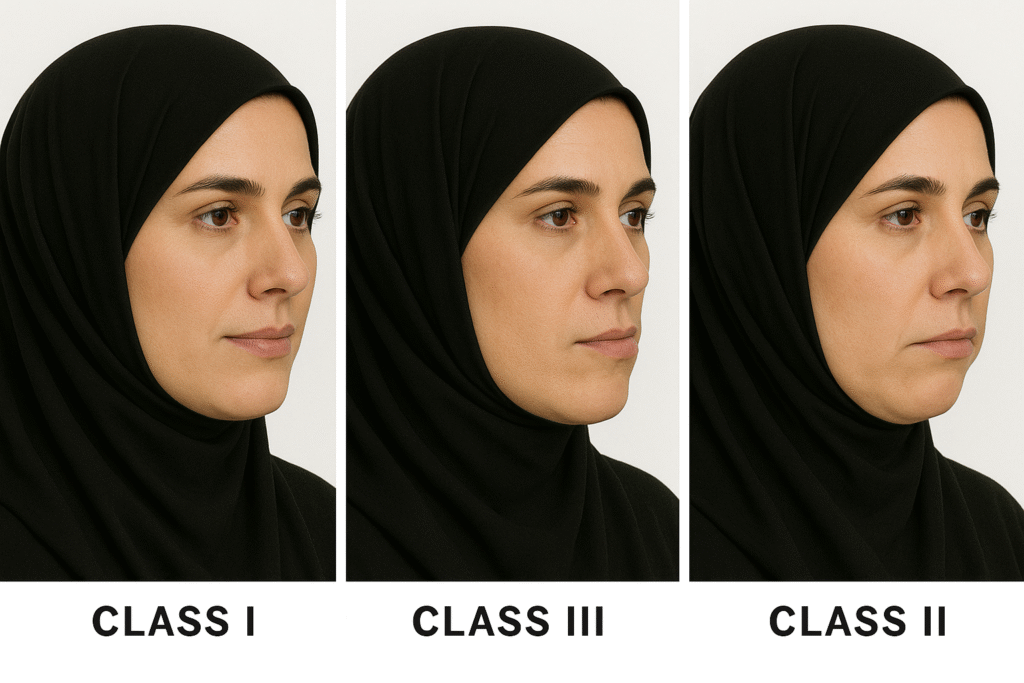

Corrective jaw surgery, also known as orthognathic surgery, is a specialized procedure designed to address irregularities in the jaw bones and realign the jaws and teeth to improve their function. This surgery can be recommended for individuals experiencing difficulties with chewing, speech, breathing, or facial symmetry due to skeletal misalignment. At Ibdaa Dental Clinic, our professional surgeons utilize advanced 3D imaging and precise digital planning to deliver personalized treatments that not only enhance your oral health, but also boost your confidence and facial aesthetics.